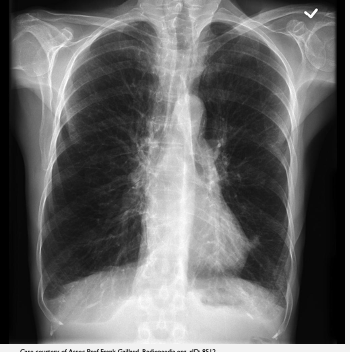

What does this CXR indicate? - Pneumoperitoneum - Pneumothorax - Pulmonary oedema - Consolidation - Pleural effusion

What does this CXR indicate? - Pneumoperitoneum - Pneumothorax - Pulmonary oedema - Consolidation **Pleural effusion: blunted costophrenic edges**